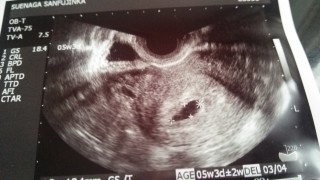

排卵検査もしていたので、計算に間違いがなければ5w3dです。 ピンクのおりものや少量の鮮血もみられていたので心配で、もう少し後の受診を予定していましたが、この日に受診してきました。 前回は5wでも確認が出来ず6w後半で流産しているのですごく不安だったんですが、前回より早い段階でしかも前より良い感じの胎嚢を確認出来ました! 赤ちゃんの素となるものも確認出来たとのことです。まんまる卵。 次回は3週間後。長いし不安ですが赤ちゃん信じて過ごします!